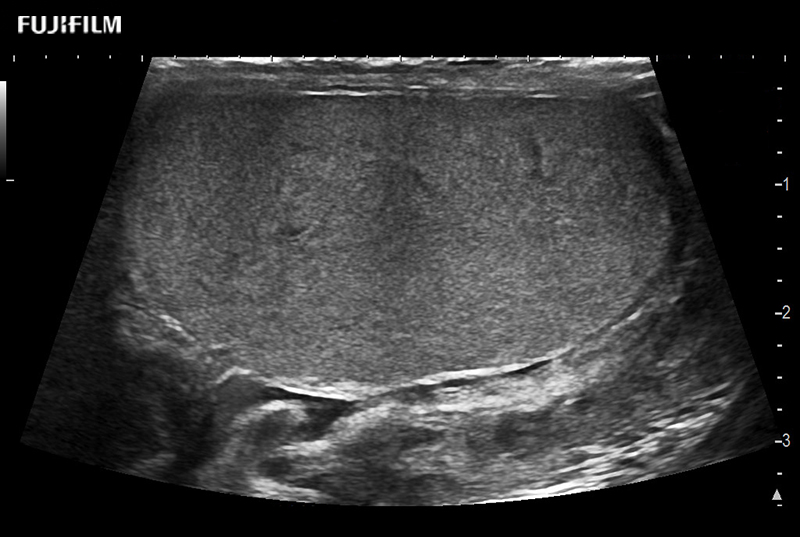

Abdominal transducer for biopsy, bladder and renal applications.